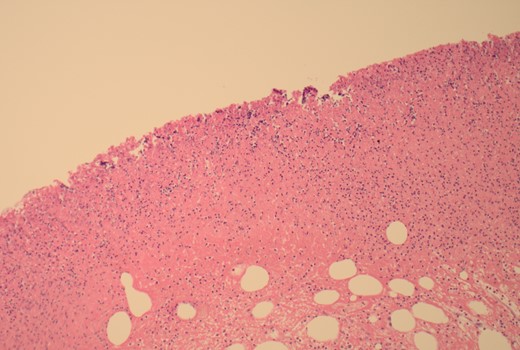

12.5× magnification showing the intact surface small bowel mucosa with the underlying lipoma.

12.5× magnification showing the junction between the ulcerated leading point of the intussusception on the left and the preserved mucosa on the right of the arrow.